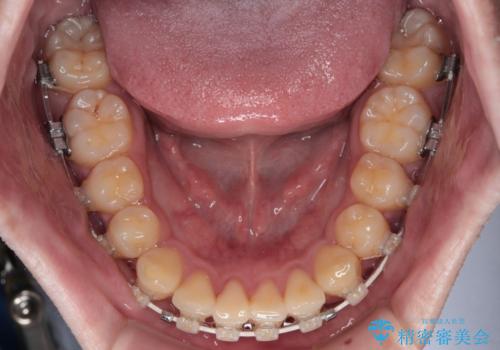

- 矯正装置

- 審美装置

昼休みを活用して通院してくださり、1年半であっという間に終えることができました。